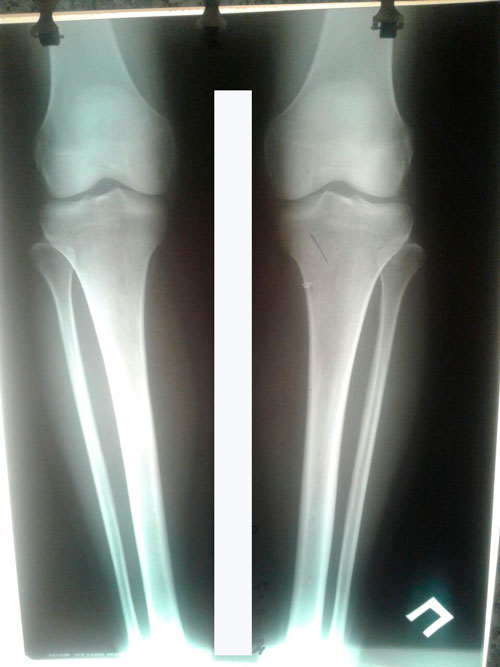

Перед крутками.

Вложения